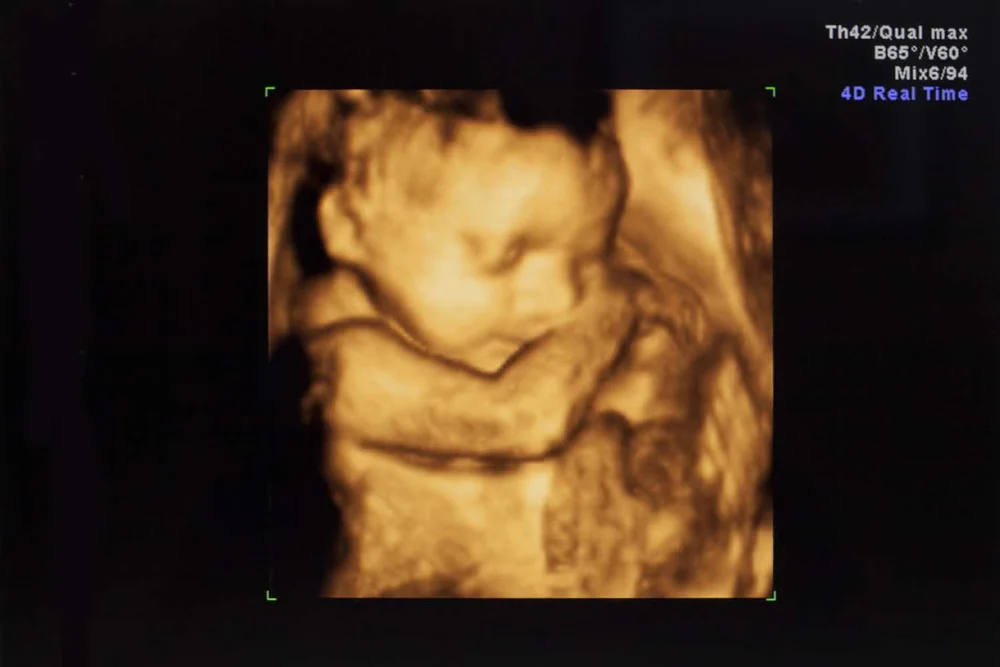

Obstetrics 3d 4d Ultrasound Helvetia Diagnostics Healthcare Center

![]() Tiny Miracles 3d 4d Prenatal Imaging Medical Centers 515 Sanitarium Rd St Helena Ca Phone Number Yelp | ![]() Tiny Miracles 3d 4d Prenatal Imaging Medical Centers 515 Sanitarium Rd St Helena Ca Phone Number Yelp | ![]() Tiny Miracles 3d 4d Prenatal Imaging Medical Centers 515 Sanitarium Rd St Helena Ca Phone Number Yelp |

![]() Tiny Miracles 3d 4d Prenatal Imaging Medical Centers 515 Sanitarium Rd St Helena Ca Phone Number Yelp | ![]() Tiny Miracles 3d 4d Prenatal Imaging Medical Centers 515 Sanitarium Rd St Helena Ca Phone Number Yelp | Tiny Miracles 3d 4d Prenatal Imaging Medical Centers 515 Sanitarium Rd St Helena Ca Phone Number Yelp |

Tiny Miracles 3d 4d Prenatal Imaging Medical Centers 515 Sanitarium Rd St Helena Ca Phone Number Yelp | ![]() Tiny Miracles 3d 4d Prenatal Imaging Medical Centers 515 Sanitarium Rd St Helena Ca Phone Number Yelp | ![]() Tiny Miracles 3d 4d Prenatal Imaging Medical Centers 515 Sanitarium Rd St Helena Ca Phone Number Yelp |

![]() Tiny Miracles 3d 4d Prenatal Imaging Medical Centers 515 Sanitarium Rd St Helena Ca Phone Number Yelp | Tiny Miracles 3d 4d Prenatal Imaging Medical Centers 515 Sanitarium Rd St Helena Ca Phone Number Yelp | Tiny Miracles 3d 4d Prenatal Imaging Medical Centers 515 Sanitarium Rd St Helena Ca Phone Number Yelp |

Tiny Miracles 3d 4d Prenatal Imaging Medical Centers 515 Sanitarium Rd St Helena Ca Phone Number Yelp | ![]() Tiny Miracles 3d 4d Prenatal Imaging Medical Centers 515 Sanitarium Rd St Helena Ca Phone Number Yelp | Tiny Miracles 3d 4d Prenatal Imaging Medical Centers 515 Sanitarium Rd St Helena Ca Phone Number Yelp |